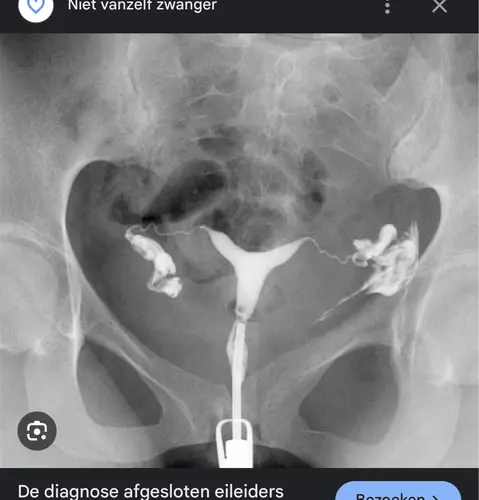

Ik heb na 1,5 jaar proberen ook een HSG gehad, diagnose: twee afgesloten eileiders. Een maand later een Foamecho gehad, diagnose: twee afgesloten eileiders.

Op de wachtlijst voor een kijkoperatie. Een dag voor de operatie een positieve test. En ondertussen een zoontje van één.

Waarschijnlijk een schrikreactie van de eileiders op de vloeistof die ze gebruiken. Ik heb me toen rot gezocht naar ervaringen, maar nergens vergelijkbare verhalen gevonden.